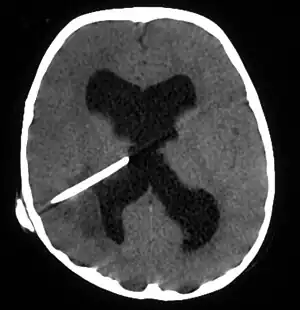

CT scans show calcified brain abscess.

The diagnosis is established by a computed tomography (CT) (with contrast) examination. At the initial phase of the inflammation (which is referred to as cerebritis), the immature lesion does not have a capsule and it may be difficult to distinguish it from other space-occupying lesions or infarcts of the brain. Within 4–5 days the inflammation and the concomitant dead brain tissue are surrounded with a capsule, which gives the lesion the famous ring-enhancing lesion appearance on CT examination with contrast (since intravenously applied contrast material can not pass through the capsule, it is collected around the lesion and looks as a ring surrounding the relatively dark lesion). Lumbar puncture procedure, which is performed in many infectious disorders of the central nervous system is contraindicated in this condition (as it is in all space-occupying lesions of the brain) because removing a certain portion of the cerebrospinal fluid may alter the concrete intracranial pressure balances and causes the brain tissue to move across structures within the skull (brain herniation).